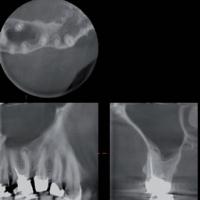

【根尖病巣】

CTスキャンは、従来のレントゲンのような平面画像(2次元)ではなく、立体画像(3次元)による高精細な断層写真を撮ることが可能です。

例えば複雑な形態をしている“根”や“骨”などもコンピューターを駆使したデータ処理と画像構成により、正確な診査・診断ができるようになりました。

CTスキャンの立体画像は、主にインプラントを含む口腔外科分野に威力を発揮しますが、断層方式パノラマX線写真や口内法X線撮影法では判別できない、痛みや症状の原因の究明にも役立っています。